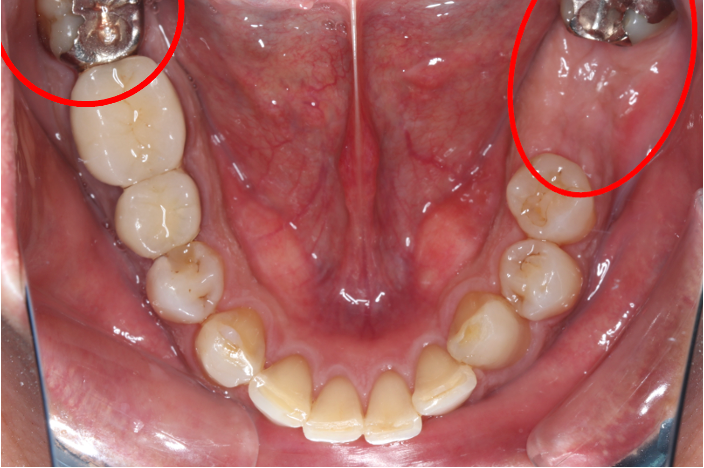

セラミック症例③

年齢30代女性

治療期間1ヶ月

治療内容セラミックインレー

治療箇所右下4番

治療費用100,000円